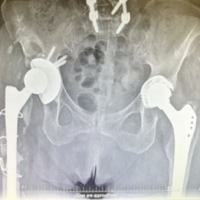

A 67-year-old female with complaints of painless swelling that progressively increased in size in the right shoulder and proximal arm for the past 8 months examination showed a palpable mass of size 8 × 5 cm non-tender with smooth surface and in the deeper planes of the shoulder girdle, mobile with firm consistency. All the shoulder movements were preserved. Plain radiographs of the right shoulder and arm were normal. Ultrasonogram showed an echogenic lesion with fluid collection in the biceps muscle plane and anterior aspect of the upper third of right arm. Magnetic resonance imaging (MRI) of the right shoulder and arm showed a well-defined space-occupying lesion of size 25 × 33 × 60 mm in the long head of biceps muscle with incomplete rupture of long head of biceps tendon at the level of supra glenoid tubercle (Fig. 1).